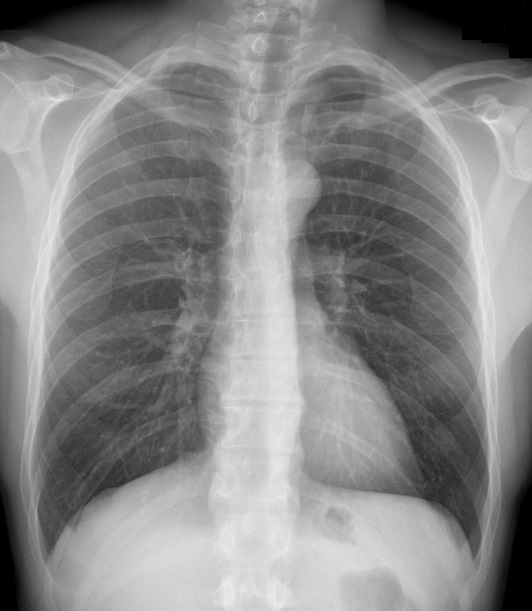

Image radiologique de

fracture de côte 4th , 5,6,7,8th droit du thorax .

Pneumothorax du poumon droit . Cliche de face PA

pulmonaire |